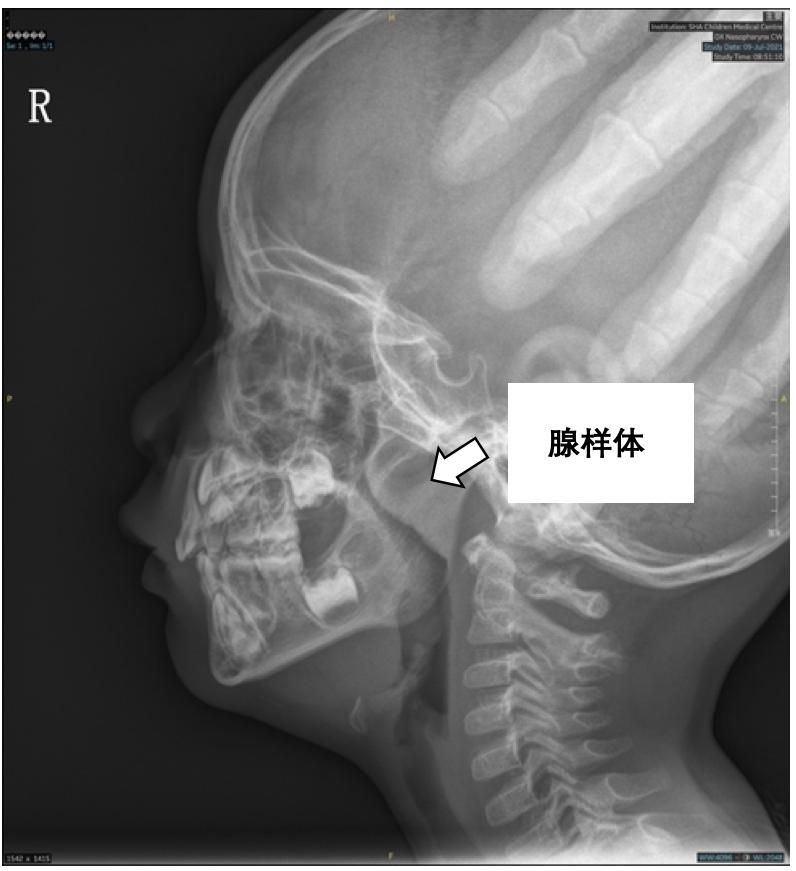

虽然爸爸安慰她说这是白天太累了,晚上睡得香,他自己小时候也是这样的。但是基于之前屡次被“猪队友”坑害的经历,妈妈觉得还是需要到医院寻求专家的建议,于是预约了呼吸哮喘/打呼噜专科就诊。医院就诊完善检查后,医生指着小朋友的鼻咽部侧位片告诉妈妈,莉莉是典型的腺样体肥大,肥大的腺样体阻塞后鼻孔90%,腺样体周围的气道被压成了“一线天”。需要进一步完善睡眠监测确认疾病的严重度,可能需要进行手术治疗。妈妈懵了,我的宝贝睡觉的时候就靠这么小的空间呼吸,能不累吗?但是这到底是个什么病啊?腺样体又是什么东西?不就是个打呼噜吗?

鼻咽部侧位片提示腺样体肥大腺样体对家长而言可能是个陌生的医学术语,腺样体是个什么结构?它到底长在哪里?腺样体又称为咽扁桃体,具有和扁桃体相类似的形态和结构,是位于鼻咽顶壁和后壁的交界处的淋巴组织。在儿童2-6岁的时候淋巴组织增生最为活跃,该年龄段是疾病发生的高峰,10-12岁开始逐渐萎缩,成年期基本消失。